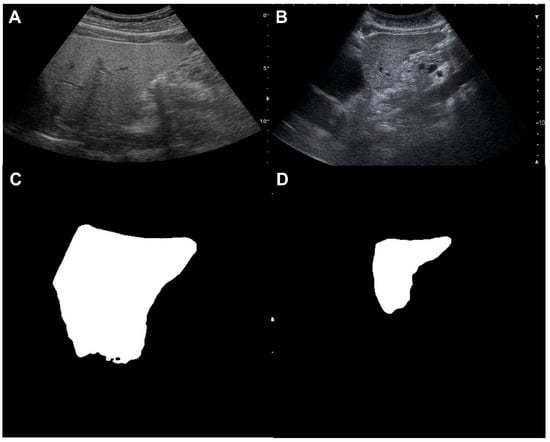

2.3. Image Pre-Processing and Machine Learning for Liver Segmentation

3.1. Accuracy of Liver Segmentation